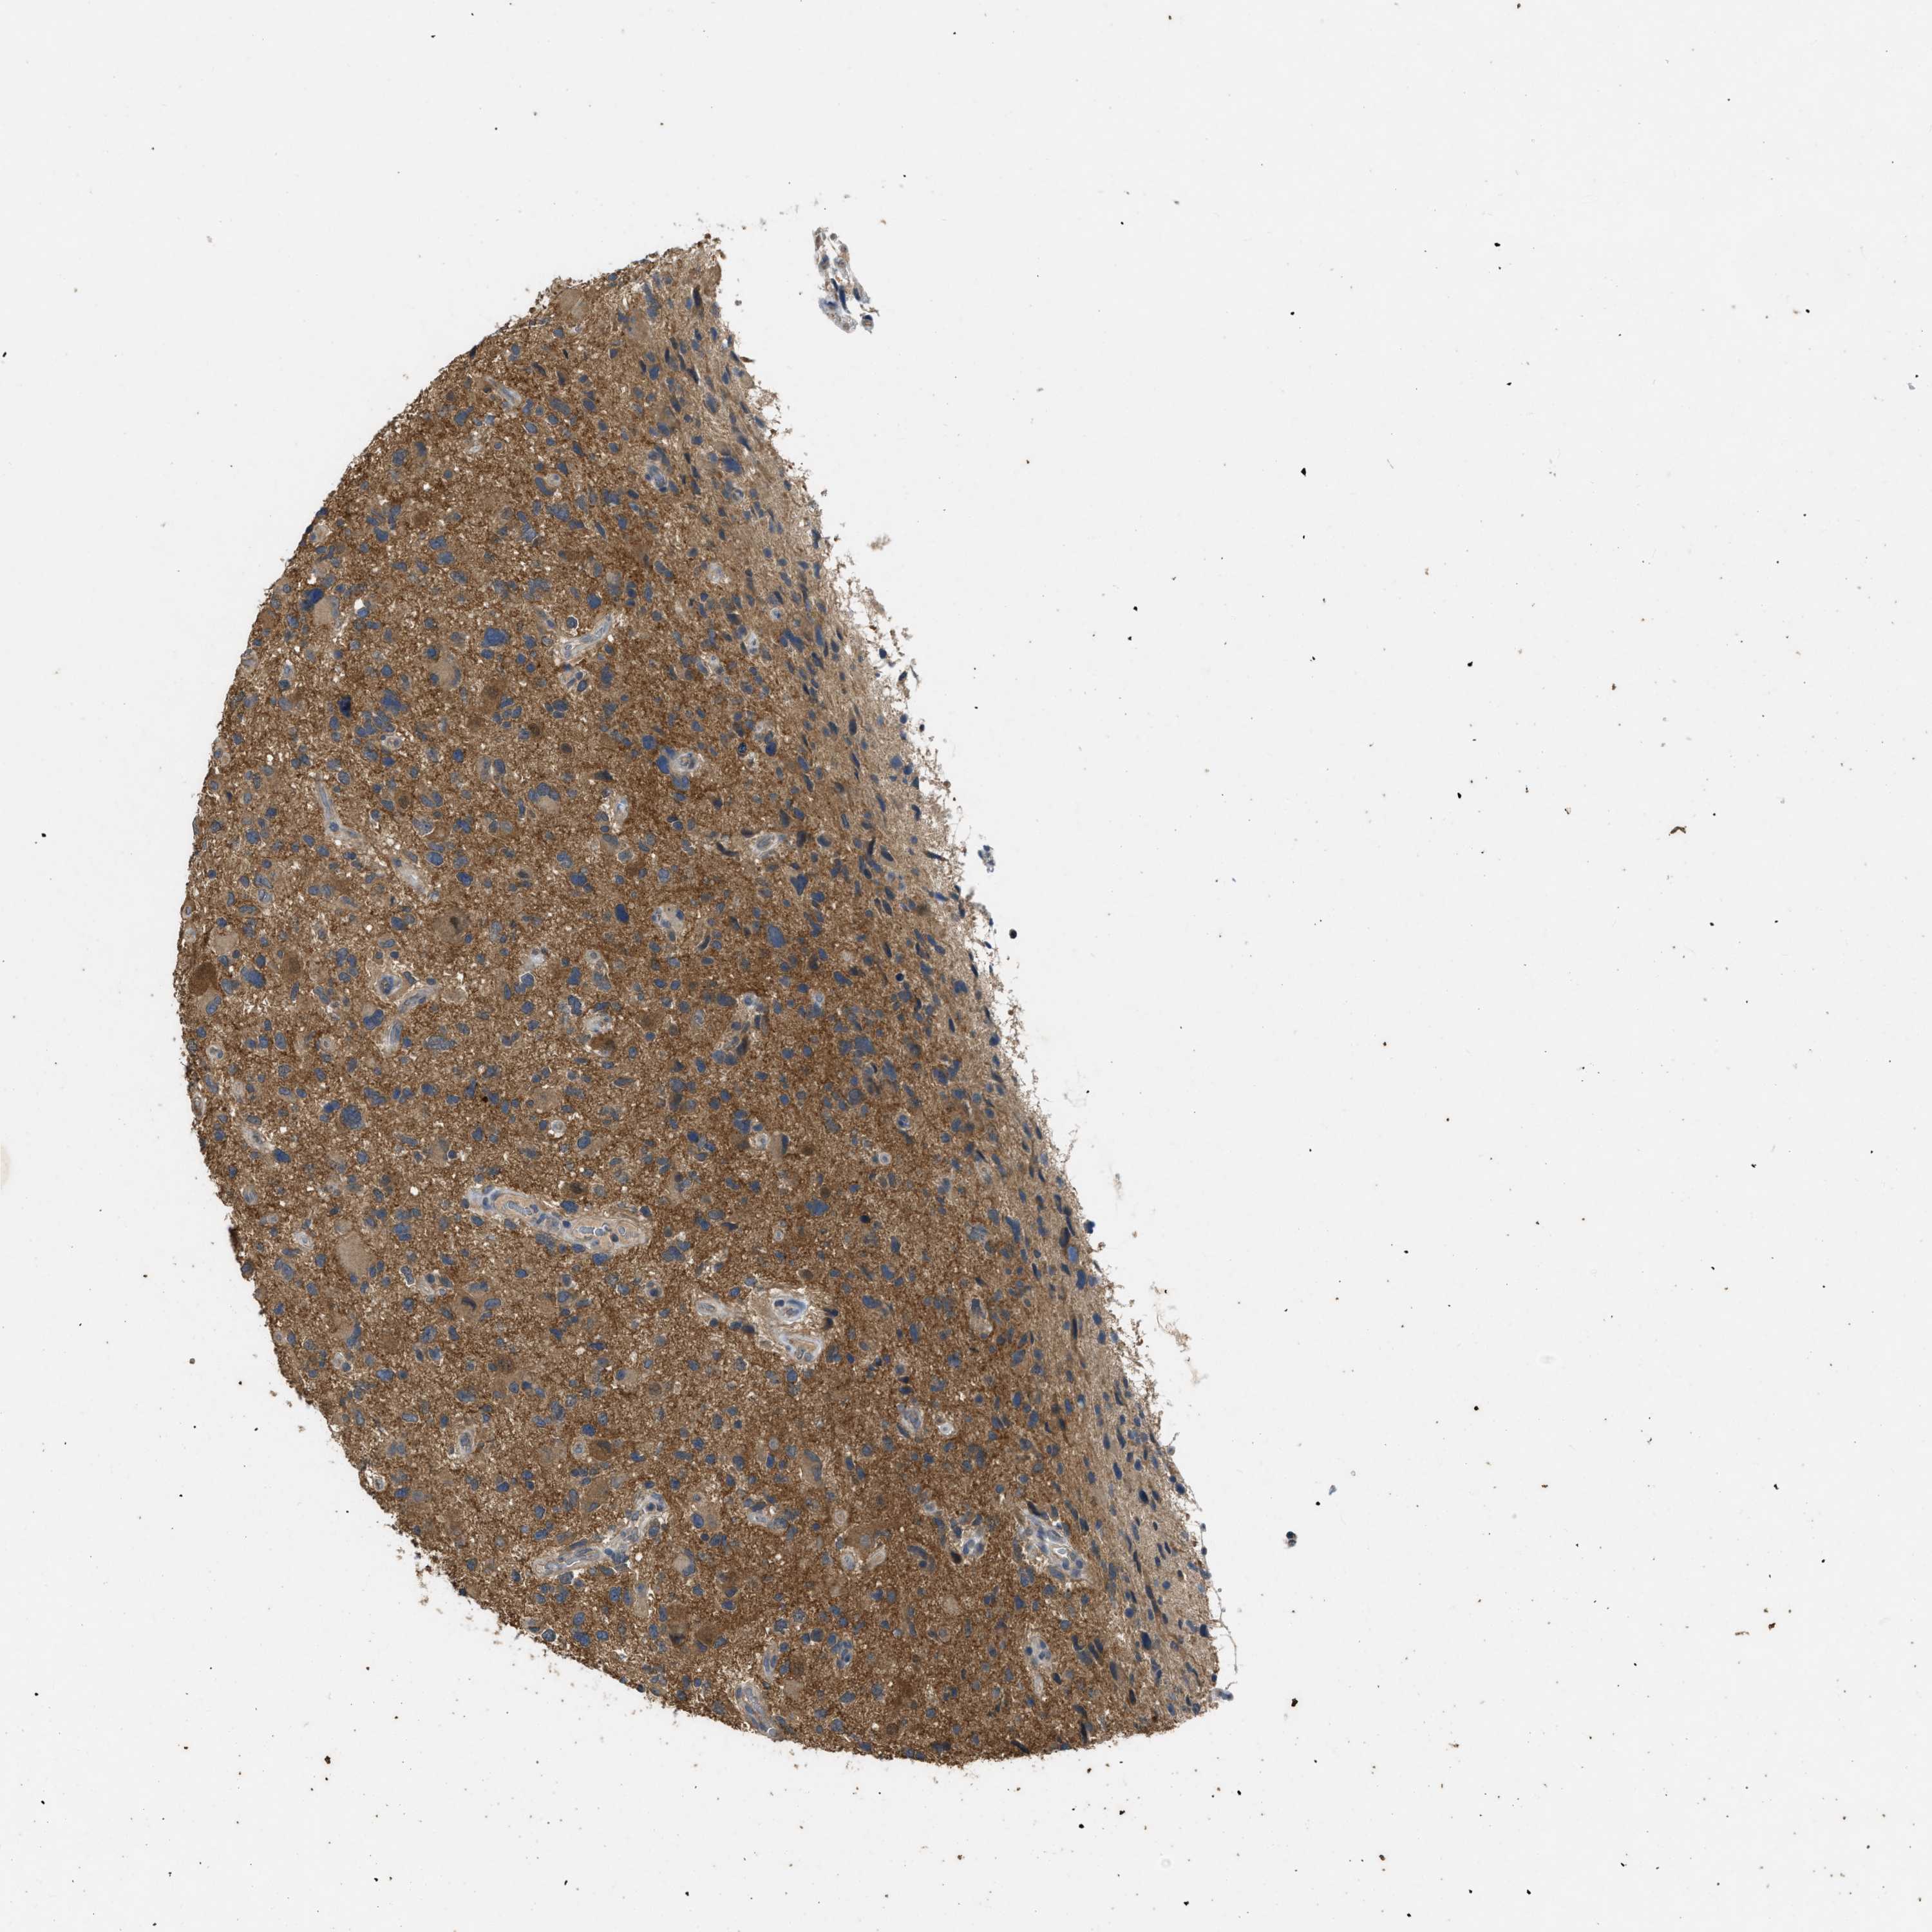

GLIOMA - Protein expressioni

A mouse-over function shows sample information and annotation data. Click on an image to view it in a full screen mode. Samples can be filtered based on level of antibody staining by selecting one or several of the following categories: high, medium, low and not detected. The assay and annotation is described here.

Note that samples used for immunohistochemistry by the Human Protein Atlas do not correspond to samples in the TCGA dataset.

Antibody stainingi

Antibody staining in the annotated cell types in the current human tissue is reported as not detected, low, medium, or high, based on conventional immunohistochemistry profiling in selected tissues. This score is based on the combination of the staining intensity and fraction of stained cells.

Each image is clickable and will lead to virtual microscopy that enables deeper exploration of all samples and also displays staining intensity scores, fraction scores and subcellular localization as well as patient and tissue information for each sample.

Antibody HPA012778

Antibody CAB018581

Staining

High

Medium

Low

Not detected

Intensity

Strong

Moderate

Weak

Negative

Quantity

>75%

75%-25%

<25%

None

Location

Nuclear

Cytoplasmic/membranous

Cytoplasmic/membranous,nuclear

Glioma, malignant, High grade

Glioma, malignant, Low grade